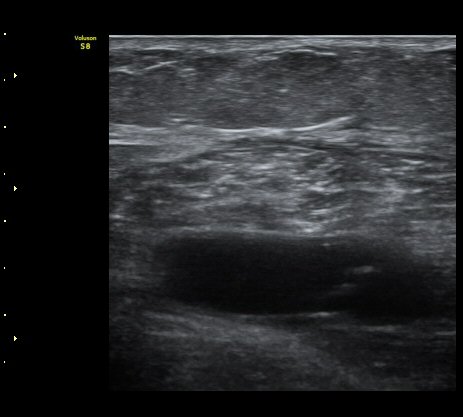

³»Ãøºñº¹±Ù°ú °¡Àڹ̱٠»çÀ̰¡ ¹ú¾îÁö°í ¼ö¾×ÀÌ Àú·ùµÊ.

ÃÊÀ½ÆÄ À¯µµÇÏ ¼ö¾× ÈíÀÎ(÷ºÎ µ¿¿µ»ó) ÈÄ ¾Ð¹ÚºØ´ë °íÁ¤.